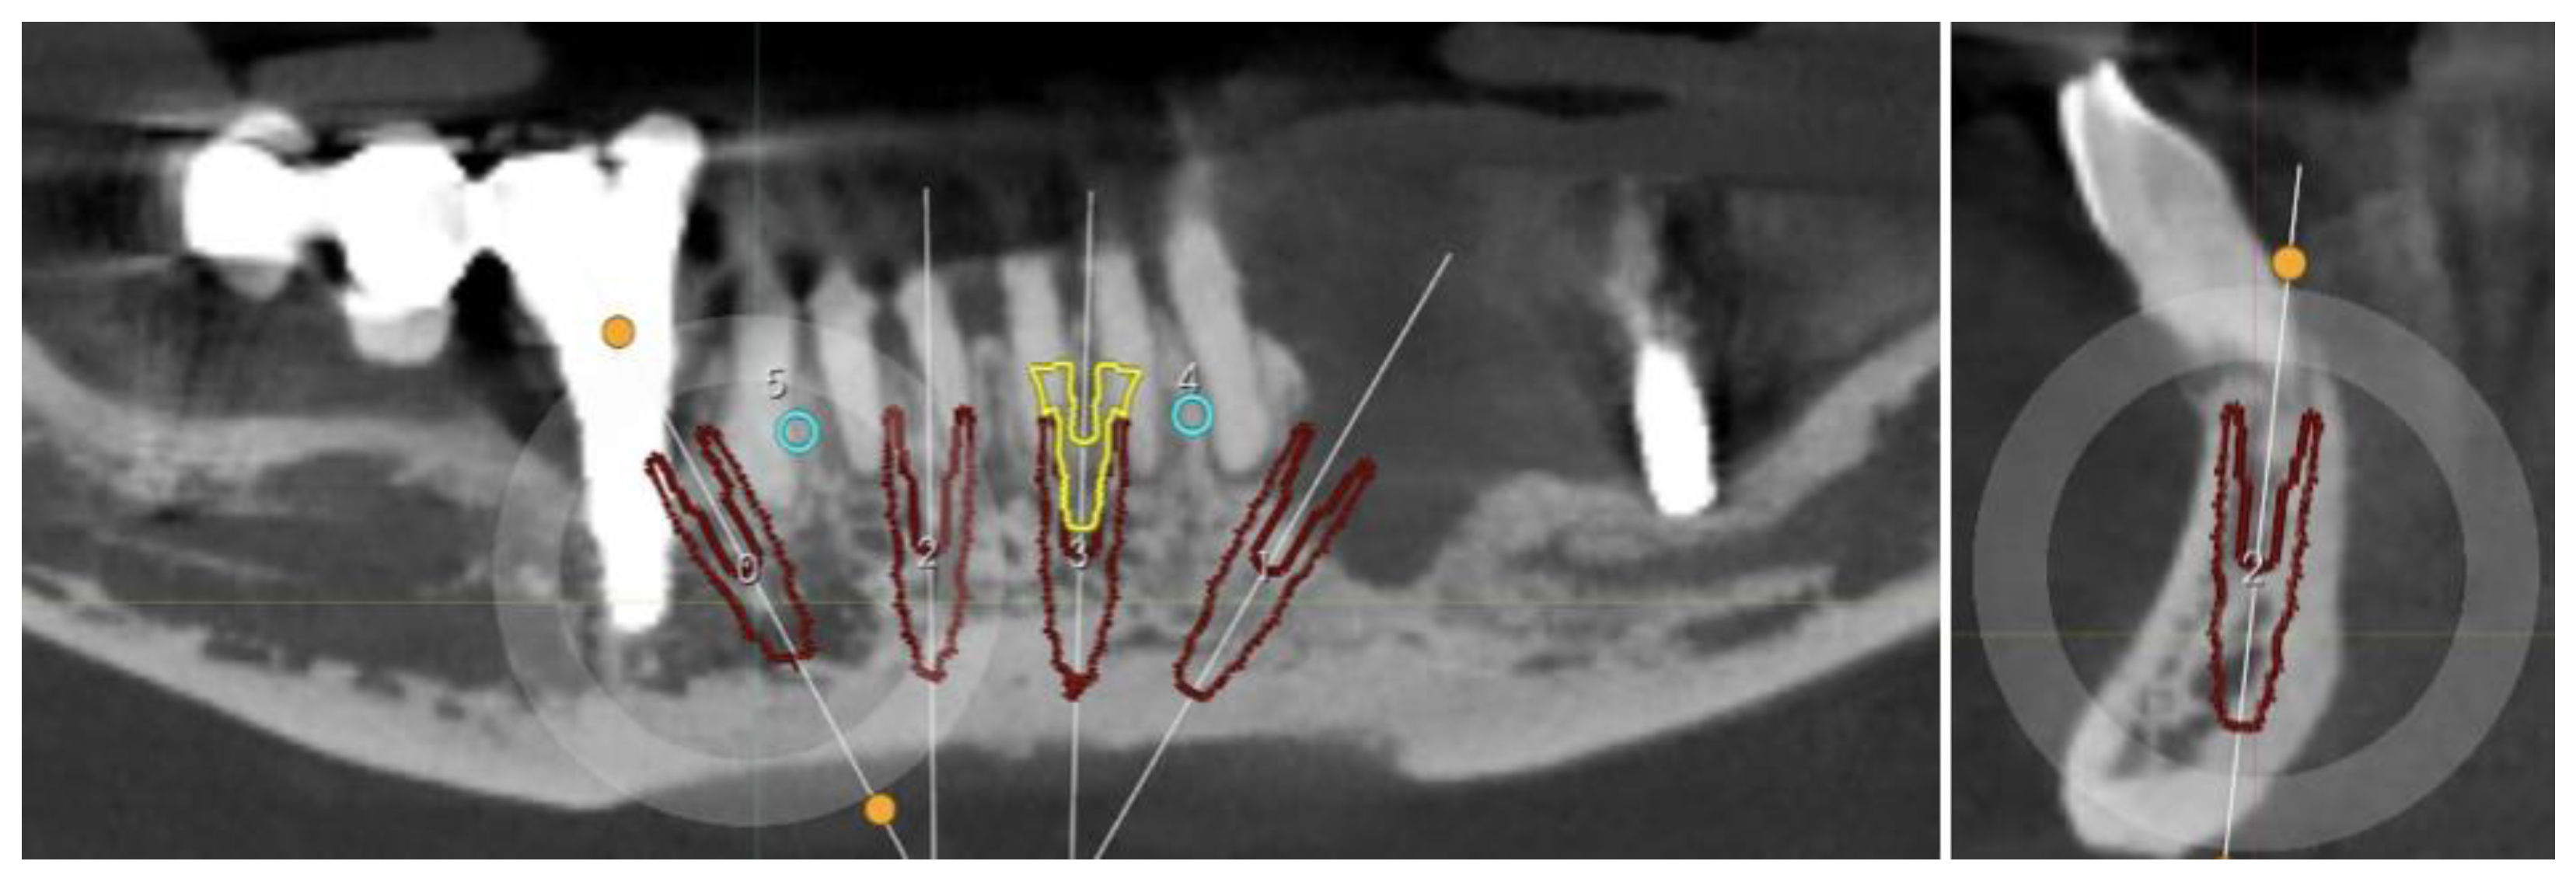

2.1. Planning

Surgical Guide

2.4. Surgery